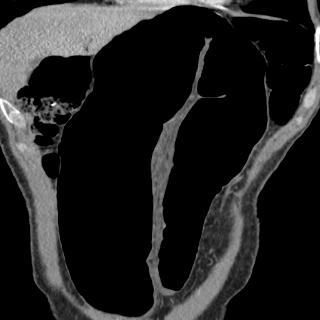

Occlusion du colon : Volvulus

du colon sigmoide en coupe axiale TDM a travers les

deux jambage de l'anse sigmoide ( etoile ) . |

|

Image TDM en coupe coronale

( frontal ) a travers une anse de volvulus du colon

sigmoide . Les deux jambages de anse sigmoide

enserrant le meso sigmoide . |

Image de volvulus du colon

sigmoide avec aspect de tourbillon au point de

volvulus . Image de tourbillon " wirhl sign"

( fleche rouge )correspondant a enroulement de l'anse autour des

vaisseaux mesenteriques |